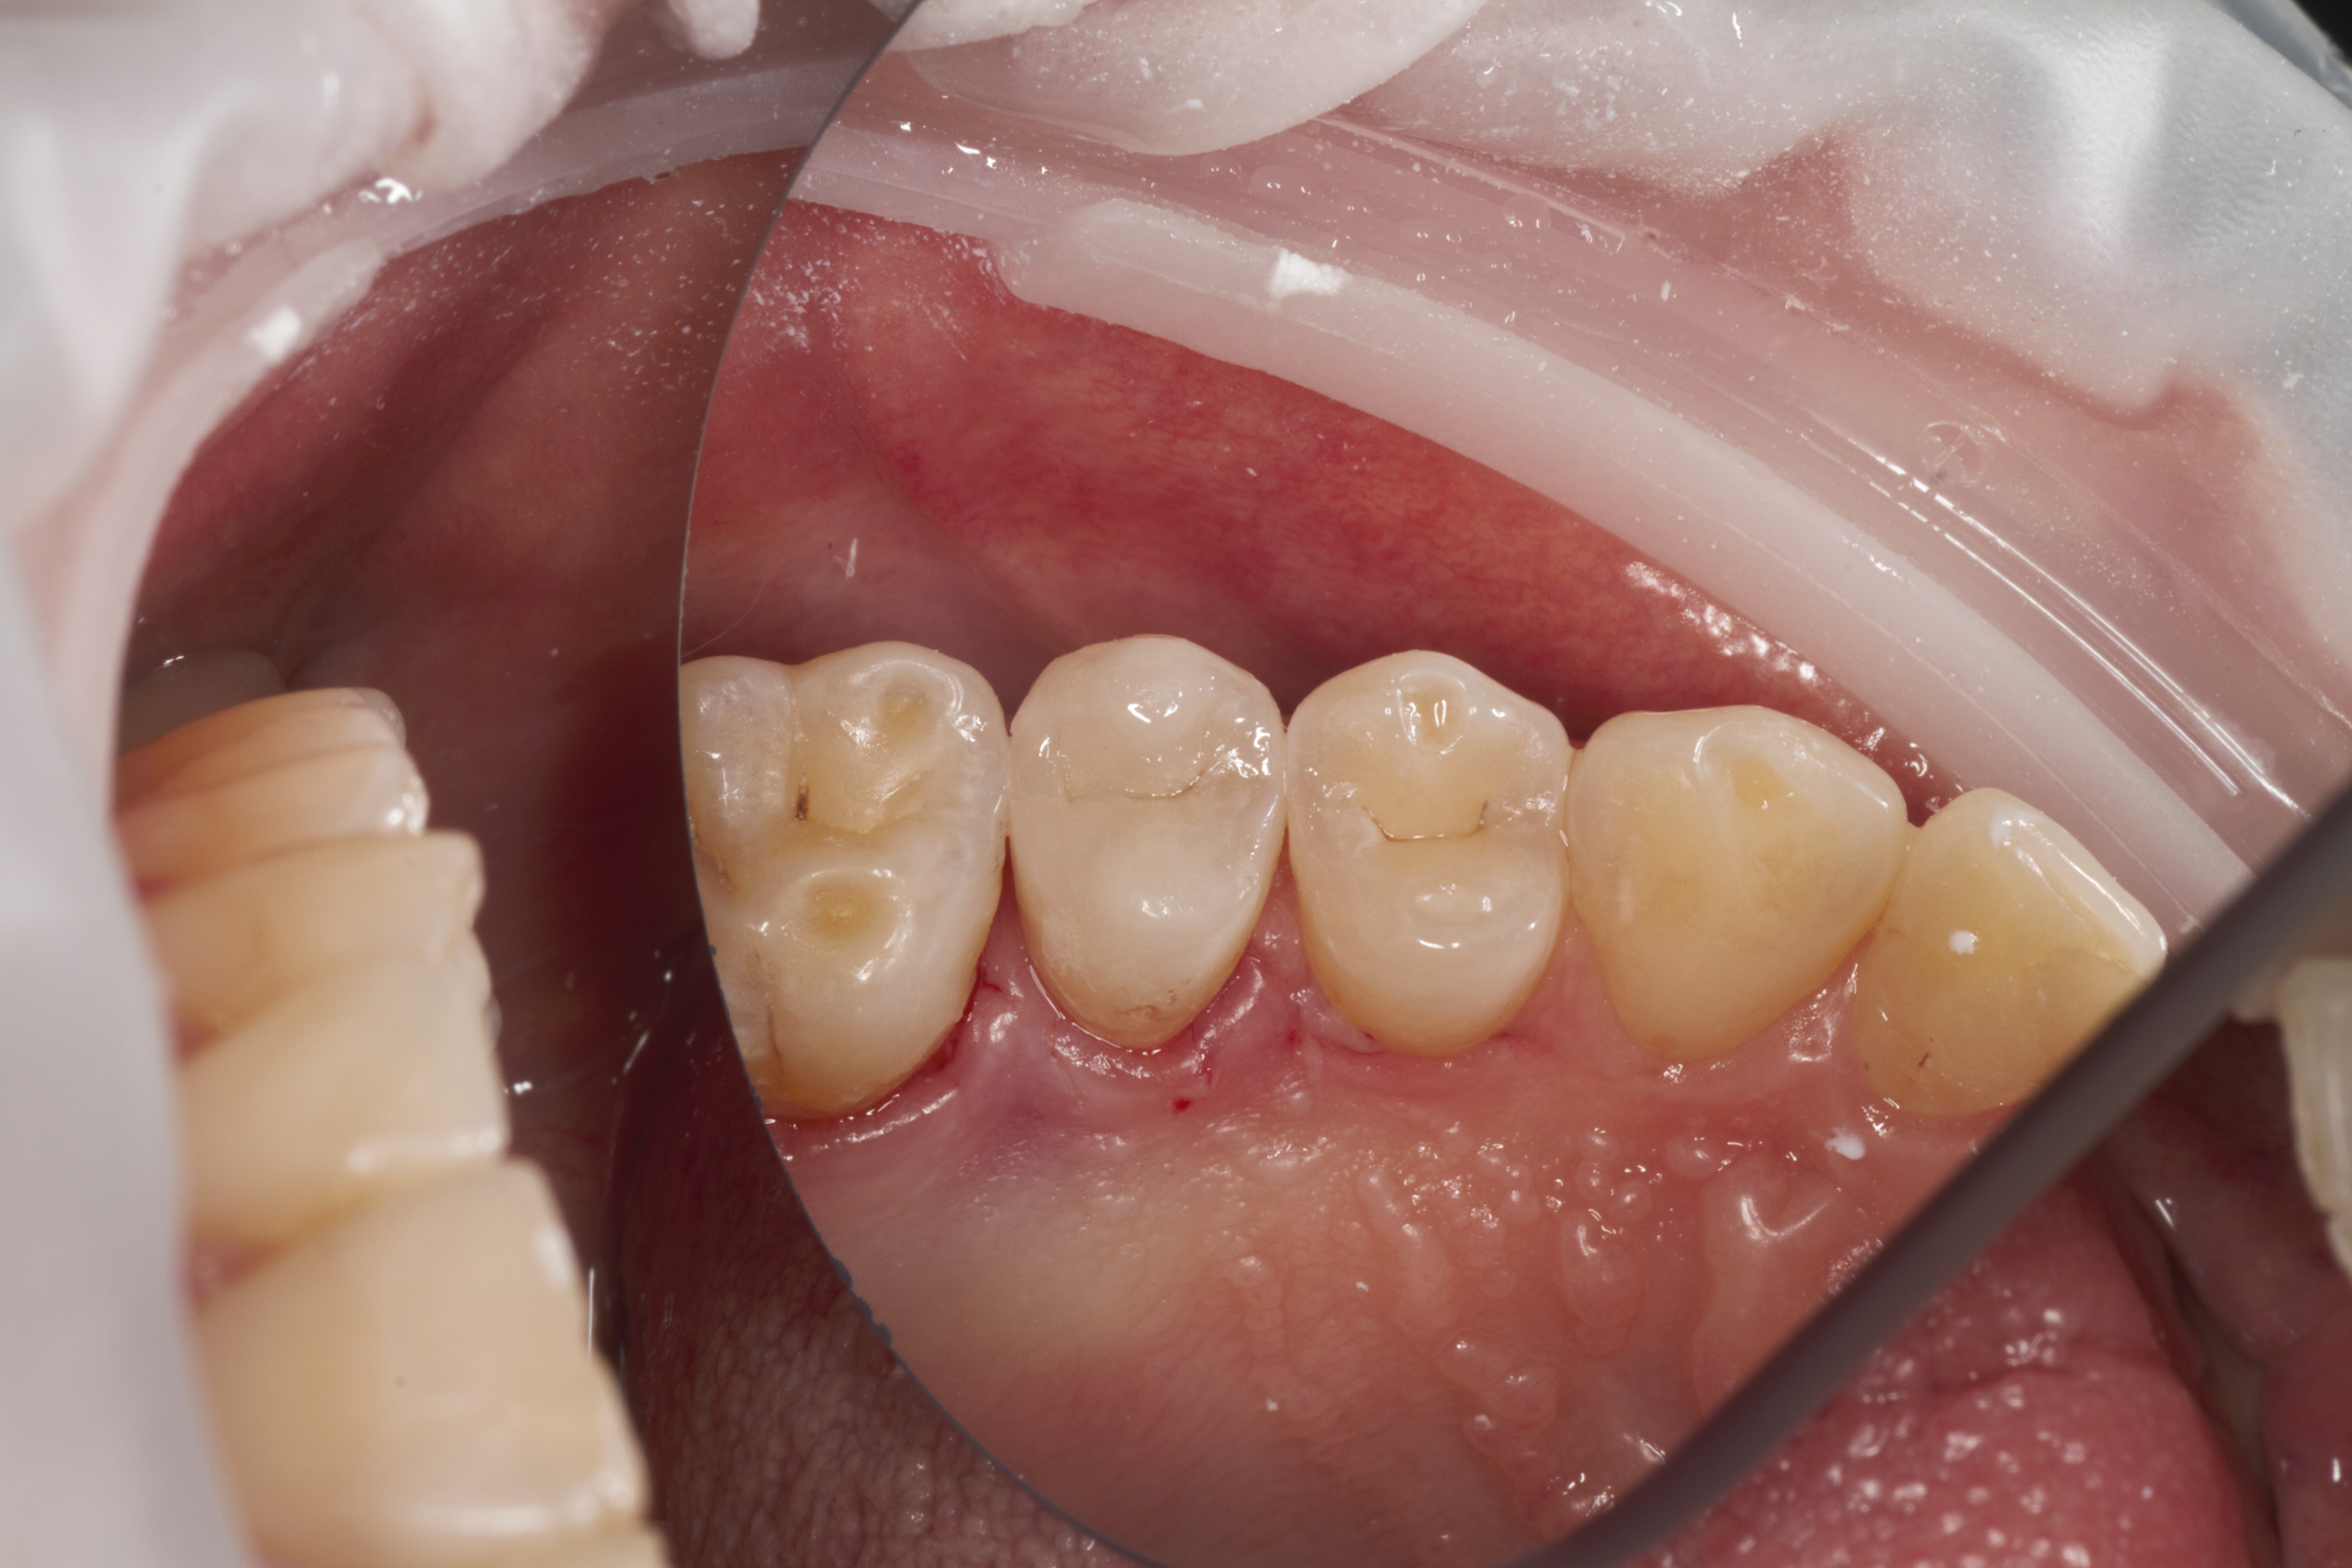

- Эстетическая реставрации жевательной и фронтальной группы зубов современными пломбировочными материалами, диагностика кариеса на ранних этапах развития, предупреждение образования вторичного кариеса в области запломбированных зубов

- Проведение полной профессиональной консультации по здоровью зубочелюстной системы, составление комплексного плана лечения, рекомендации по поддержанию качественной гигиены полости рта, обучение правильной технике чистки зубов, анализ снимков на визиографе и рентген-аппарате, анализ Клкт снимков